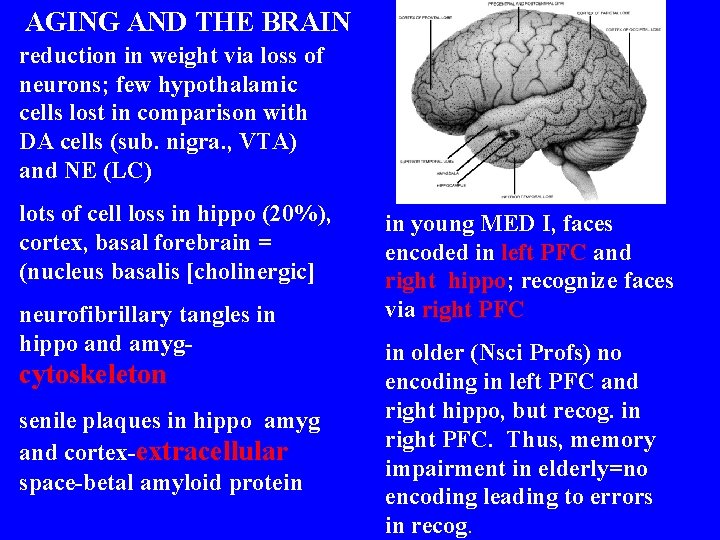

AGING AND THE BRAIN reduction in weight via loss of neurons; few hypothalamic cells lost in comparison with DA cells (sub. nigra. , VTA) and NE (LC) lots of cell loss in hippo (20%), cortex, basal forebrain = (nucleus basalis [cholinergic] neurofibrillary tangles in hippo and amyg- cytoskeleton senile plaques in hippo amyg and cortex-extracellular space-betal amyloid protein in young MED I, faces encoded in left PFC and right hippo; recognize faces via right PFC in older (Nsci Profs) no encoding in left PFC and right hippo, but recog. in right PFC. Thus, memory impairment in elderly=no encoding leading to errors in recog.